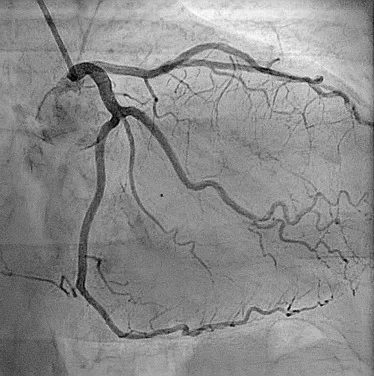

Coronary Angiography is a specialized diagnostic procedure used to visualize the blood flow in your heart’s arteries. It helps detect blockages or narrowing in the coronary arteries, which can lead to chest pain (angina), heart attacks, or other cardiac conditions. It’s considered the gold standard for evaluating coronary artery disease (CAD).

• A special dye (contrast) is injected into the coronary arteries.

• Real-time X-ray images (angiograms) show the flow of blood in your heart.